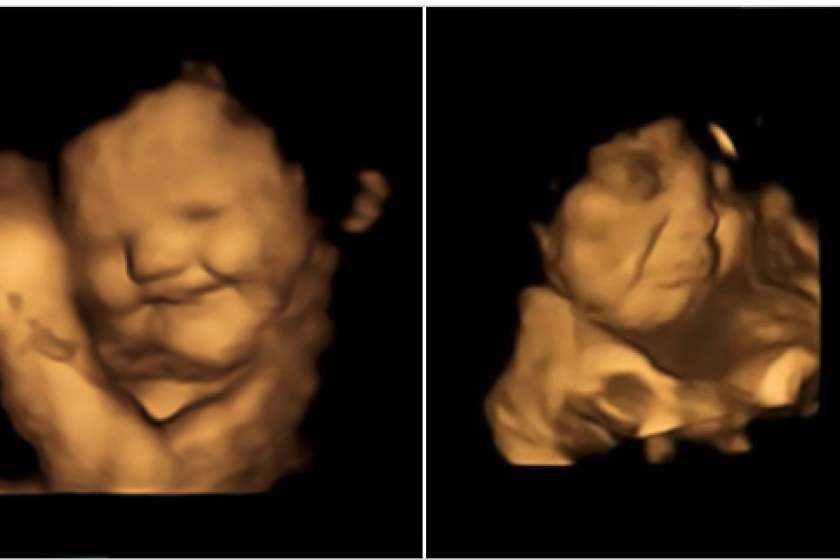

On the left is a baby happily responding to the sweet taste of carrot and on the right is a baby grimacing at the bitter taste of kaleFETAP (Fetal Taste Preferences) Study, Fetal and Neonatal Research Lab, Durham University

An extraordinary new study has recorded the first evidence of babies in the womb reacting to flavors of foods eaten by their mothers. The stunning images show fetuses crumpling up their faces in disgust minutes after a mother consumes bitter kale or smiling with glee in the presence of sweet carrot flavors.

“A number of studies have suggested that babies can taste and smell in the womb, but they are based on post-birth outcomes while our study is the first to see these reactions prior to birth,” explained lead researcher on the new study, Beyza Ustun.